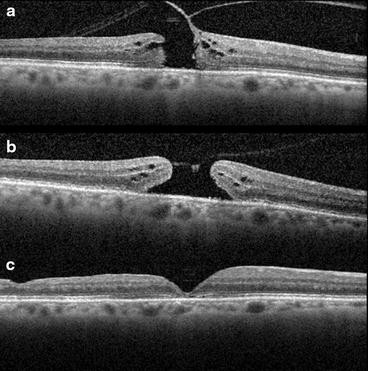

Advances in ophthalmic imaging have focused our understanding of disorders involving the vitreomacular interface. In 2013, the International Vitreomacular Traction Study (IVTS) Group introduced an optical coherence tomography (OCT) based system for the classification of vitreomacular interface disease [2]. Specifically, the terms vitreomacular adhesion (VMA), vitreomacular traction (VMT), and full-thickness macular hole (FTMH) were defined. FTMH was defined as a foveal lesion involving all retinal layers. VMA was defined as macular attachment of the vitreous cortex within a 3-mm radius of the fovea without change in retinal morphology. VMT was differentiated from VMA by the presence of retinal morphologic changes, but without FTMH (Fig. 1). Both VMA and VMT could be further classified by the size of adhesion [focal (≤1500 μm) or diffuse (>1500 μm)] as well as the presence or absence of concurrent macular disease. FTMH was classified as primary (due to VMT) or secondary and further defined by size as small (≤250 μm), medium (>250 and ≤400 μm), or large (>400 μm).

Examples of vitreomacular traction (VMT) and full thickness macular hole (FTMH). The International Vitreomacular Traction Study (IVTS) Group defined abnormalities of the vitreoretinal interface. Vitreomacular adhesion (VMA) was defined as macular attachment of the vitreous cortex within a 3-mm radius of the fovea without change in retinal morphology. VMT was differentiated from VMA by the presence of retinal morphologic changes (a, b) but without full-thickness defect. FTMH was defined as a foveal lesion involving all retinal layers (c)